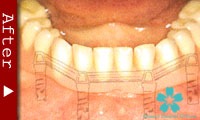

歯が全くない場合

下顎の歯が1本もない場合の修復には、インプラントが良く利用されます。

インプラントのヘッド部をバー状の維持装置で連結し、その上に取り外し式の入れ歯をしっかりと固定することができます。